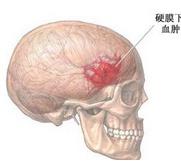

亚急性硬膜外血肿

628健康网为您分享有关亚急性硬膜外血肿的症状,亚急性硬膜外血肿的治疗方法,亚急性硬膜外血肿的预防知识,亚急性硬膜外血...

急性硬脑膜下血肿

628健康网为您分享有关急性硬脑膜下血肿的症状,急性硬脑膜下血肿的治疗方法,急性硬脑膜下血肿的预防知识,急性硬脑膜下血...

慢性硬脑膜下血肿

628健康网为您分享有关慢性硬脑膜下血肿的症状,慢性硬脑膜下血肿的治疗方法,慢性硬脑膜下血肿的预防知识,慢性硬脑膜下血...